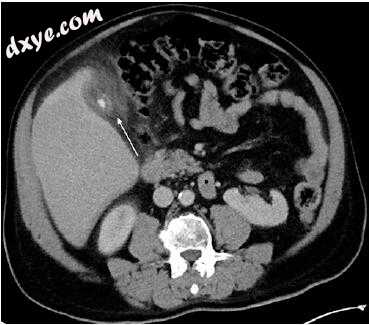

胆总管囊肿涉及肝外胆管任何部分的先天性囊性扩张,大多数胆总管囊肿在儿童时期被诊断出来;然而,高达20%无论是否存在胆管扩张,都应仔细检查可见的导管以识别和表征填充缺陷,其中绝大多数代表结石。胆管结石在CT上的可检测性取决于钙含量,并且需要预先对比CT。根据组成,结石可能表现出软组织衰减,近水衰减或周围钙化引起的脂肪减少。在T2加权成像或MRCP上,石头表现为信号无效(图5.1)。在T1加权成像中,胆固醇结石通常是等信号或低信号,而色素结石由于金属离子的存在而呈高信号。 ERCP对于小胆总管结石的检测非常准确,并且还提供治疗干预的途径。

图5.1在冠状动脉T2加权屏气MR序列上看到70岁男性肝胆管结石患者(箭头)在肝胰管的胰后部分。注意蝶翠诗在慢性发炎胆囊中的扩张和进一步的凝固